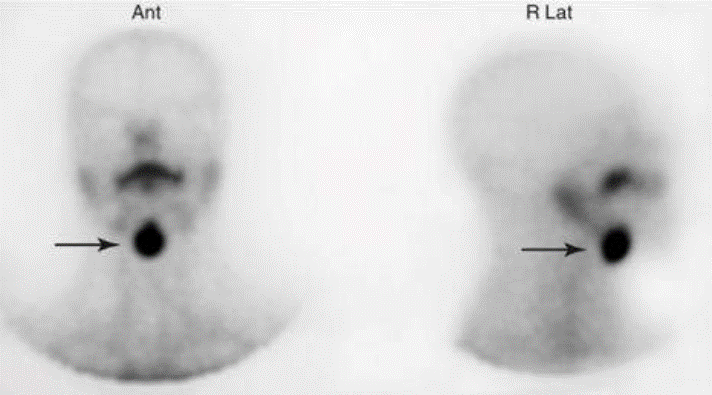

Sobre o estudo com pertecnetato-99mTc abaixo, assinale a alternativa correta.

É compatível com tireoide sublingual.

Representa um achado de nódulo autônomo de tireoide.